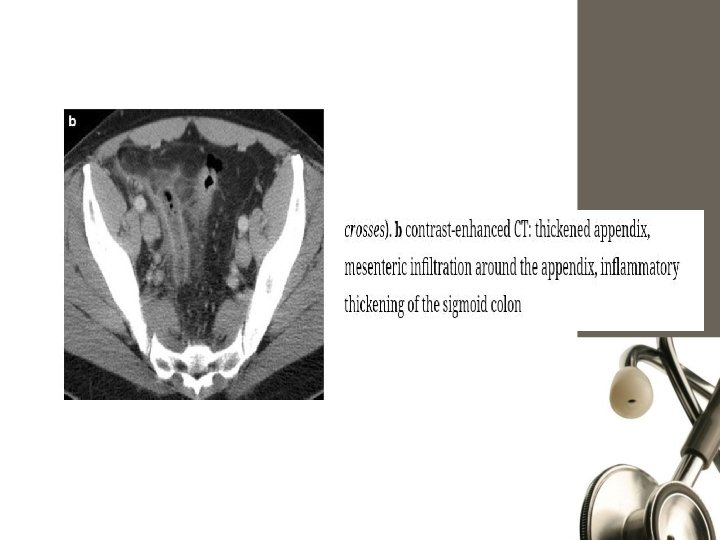

computed tomography (CT) scan - Appendix dilated and the wall is thickened. Periappendiceal phlegmon, and free fluid Periappendiceal fat stranding Thickened mesoappendix Fecaliths but their presence is not pathognomonic of appendicitis.

Ultrasonography. sensitivity of 55% to 96% and a specificity of 85% to 98%. (CT) scan 92% to 97% sensitivity, 85% to 94% specificity

Computed Tomography • Rational use: - Elderly - Atypical presentations - Neoplasms - Acute diverticulits - Intestinal obstruction • MRI: ? ?